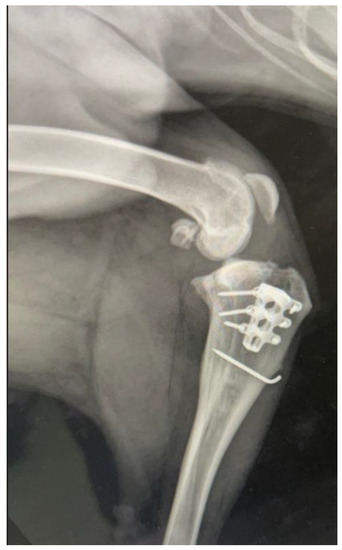

:Simple Summary

2. Detailed Case Description